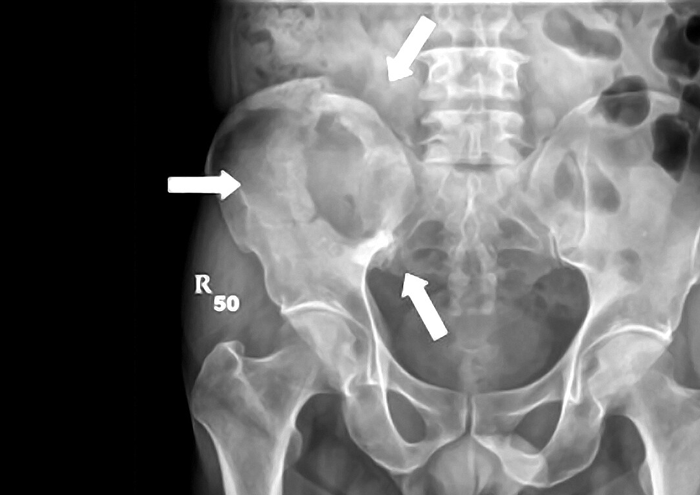

استئوسارکوم شایعترین تومور بدخیم اولیه استخوان در نوجوانان و جوانان است، اما احتمال اینکه در بزرگسالان هم رخ دهد، وجود دارد، به ویژه در استخوانهای لگن. این تومور با تولید استخوان غیرطبیعی (osteoid) شناخته میشود و رفتار تهاجمی دارد. در لگن، پیشآگهی معمولاً ضعیفتر از استخوانهای اندامهاست، زیرا جراحی کامل دشوارتر است و احتمال باقیماندن بخشی از تومور یا عود محلی بالاتر است. درمان استاندارد شامل شیمیدرمانی قبل از جراحی، جراحی با حاشیه وسیع و در صورت لزوم بازسازی استخوانی است. علائم بالینی این تومور به صورت درد مداوم، تورم، و گاهی شکستگی پاتولوژیک بروز میکند.